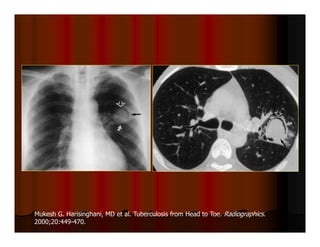

Mukesh G. Harisinghani, MD et al. Tuberculosis from Head to Toe. Radiographics.

2000;20:449-470.